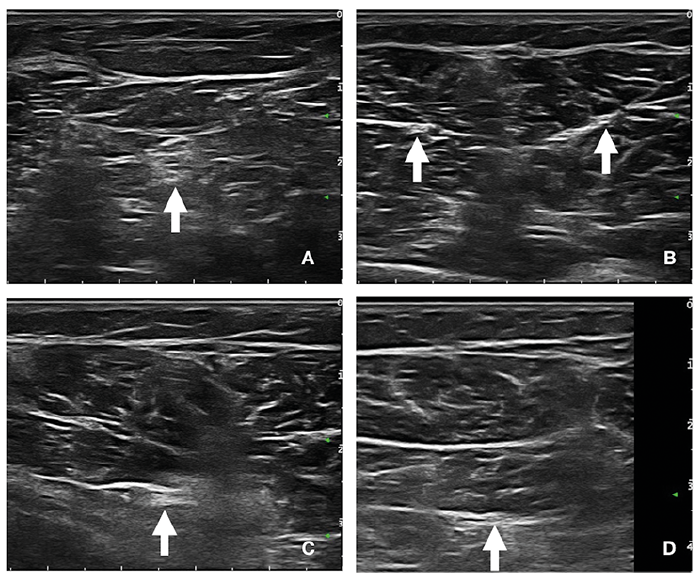

The mean coordinates for the gastrocnemius medialis motor branch were 1.5 cm (standard deviation (SD) 2.7) vertical (proximal to the fibular head), 1.7 cm (SD 1.3) horizontal (medial to the virtual line extending from the middle of popliteal fossa to the Achilles tendon insertion), and 1.1 cm (SD 0.4) deep (distance from the skin). The mean coordinates for the gastrocnemius lateralis motor branch were 0.9 cm (SD 2.2) vertical (proximal to the fibular head), 1.8 cm (SD 1.7) horizontal (lateral to the virtual line extending from the middle of popliteal fossa to the Achilles tendon insertion), and 1.0 cm (SD 0.3) deep (distance from the skin). The mean coordinates for the soleus motor branch were 1.4 cm (SD 1.1) vertical (distal to the fibular head), 1.6 cm (SD 0.7) horizontal (lateral to the virtual line extending from the middle of popliteal fossa to the Achilles tendon insertion), and 2.8 cm (SD 0.7) deep (distance from the skin). The mean coordinates for the tibialis posterior motor branch were 4.3 cm (SD 1.5) vertical (distal to the fibular head), 1.9 cm (SD 0.9) horizontal (lateral to the virtual line extending from the middle of popliteal fossa to the Achilles tendon insertion), and 4.2 cm (SD 0.8) deep (distance from the skin). US images of tibial motor nerve branches to the gastrocnemii, soleus and tibialis posterior muscles are shown in Fig. 1.

Fig. 1. Ultrasound images of: (A) the tibial nerve trunk, and its motor branches to (B) the gastrocnemii muscle, (C) soleus muscle, and (D) tibialis posterior muscle.